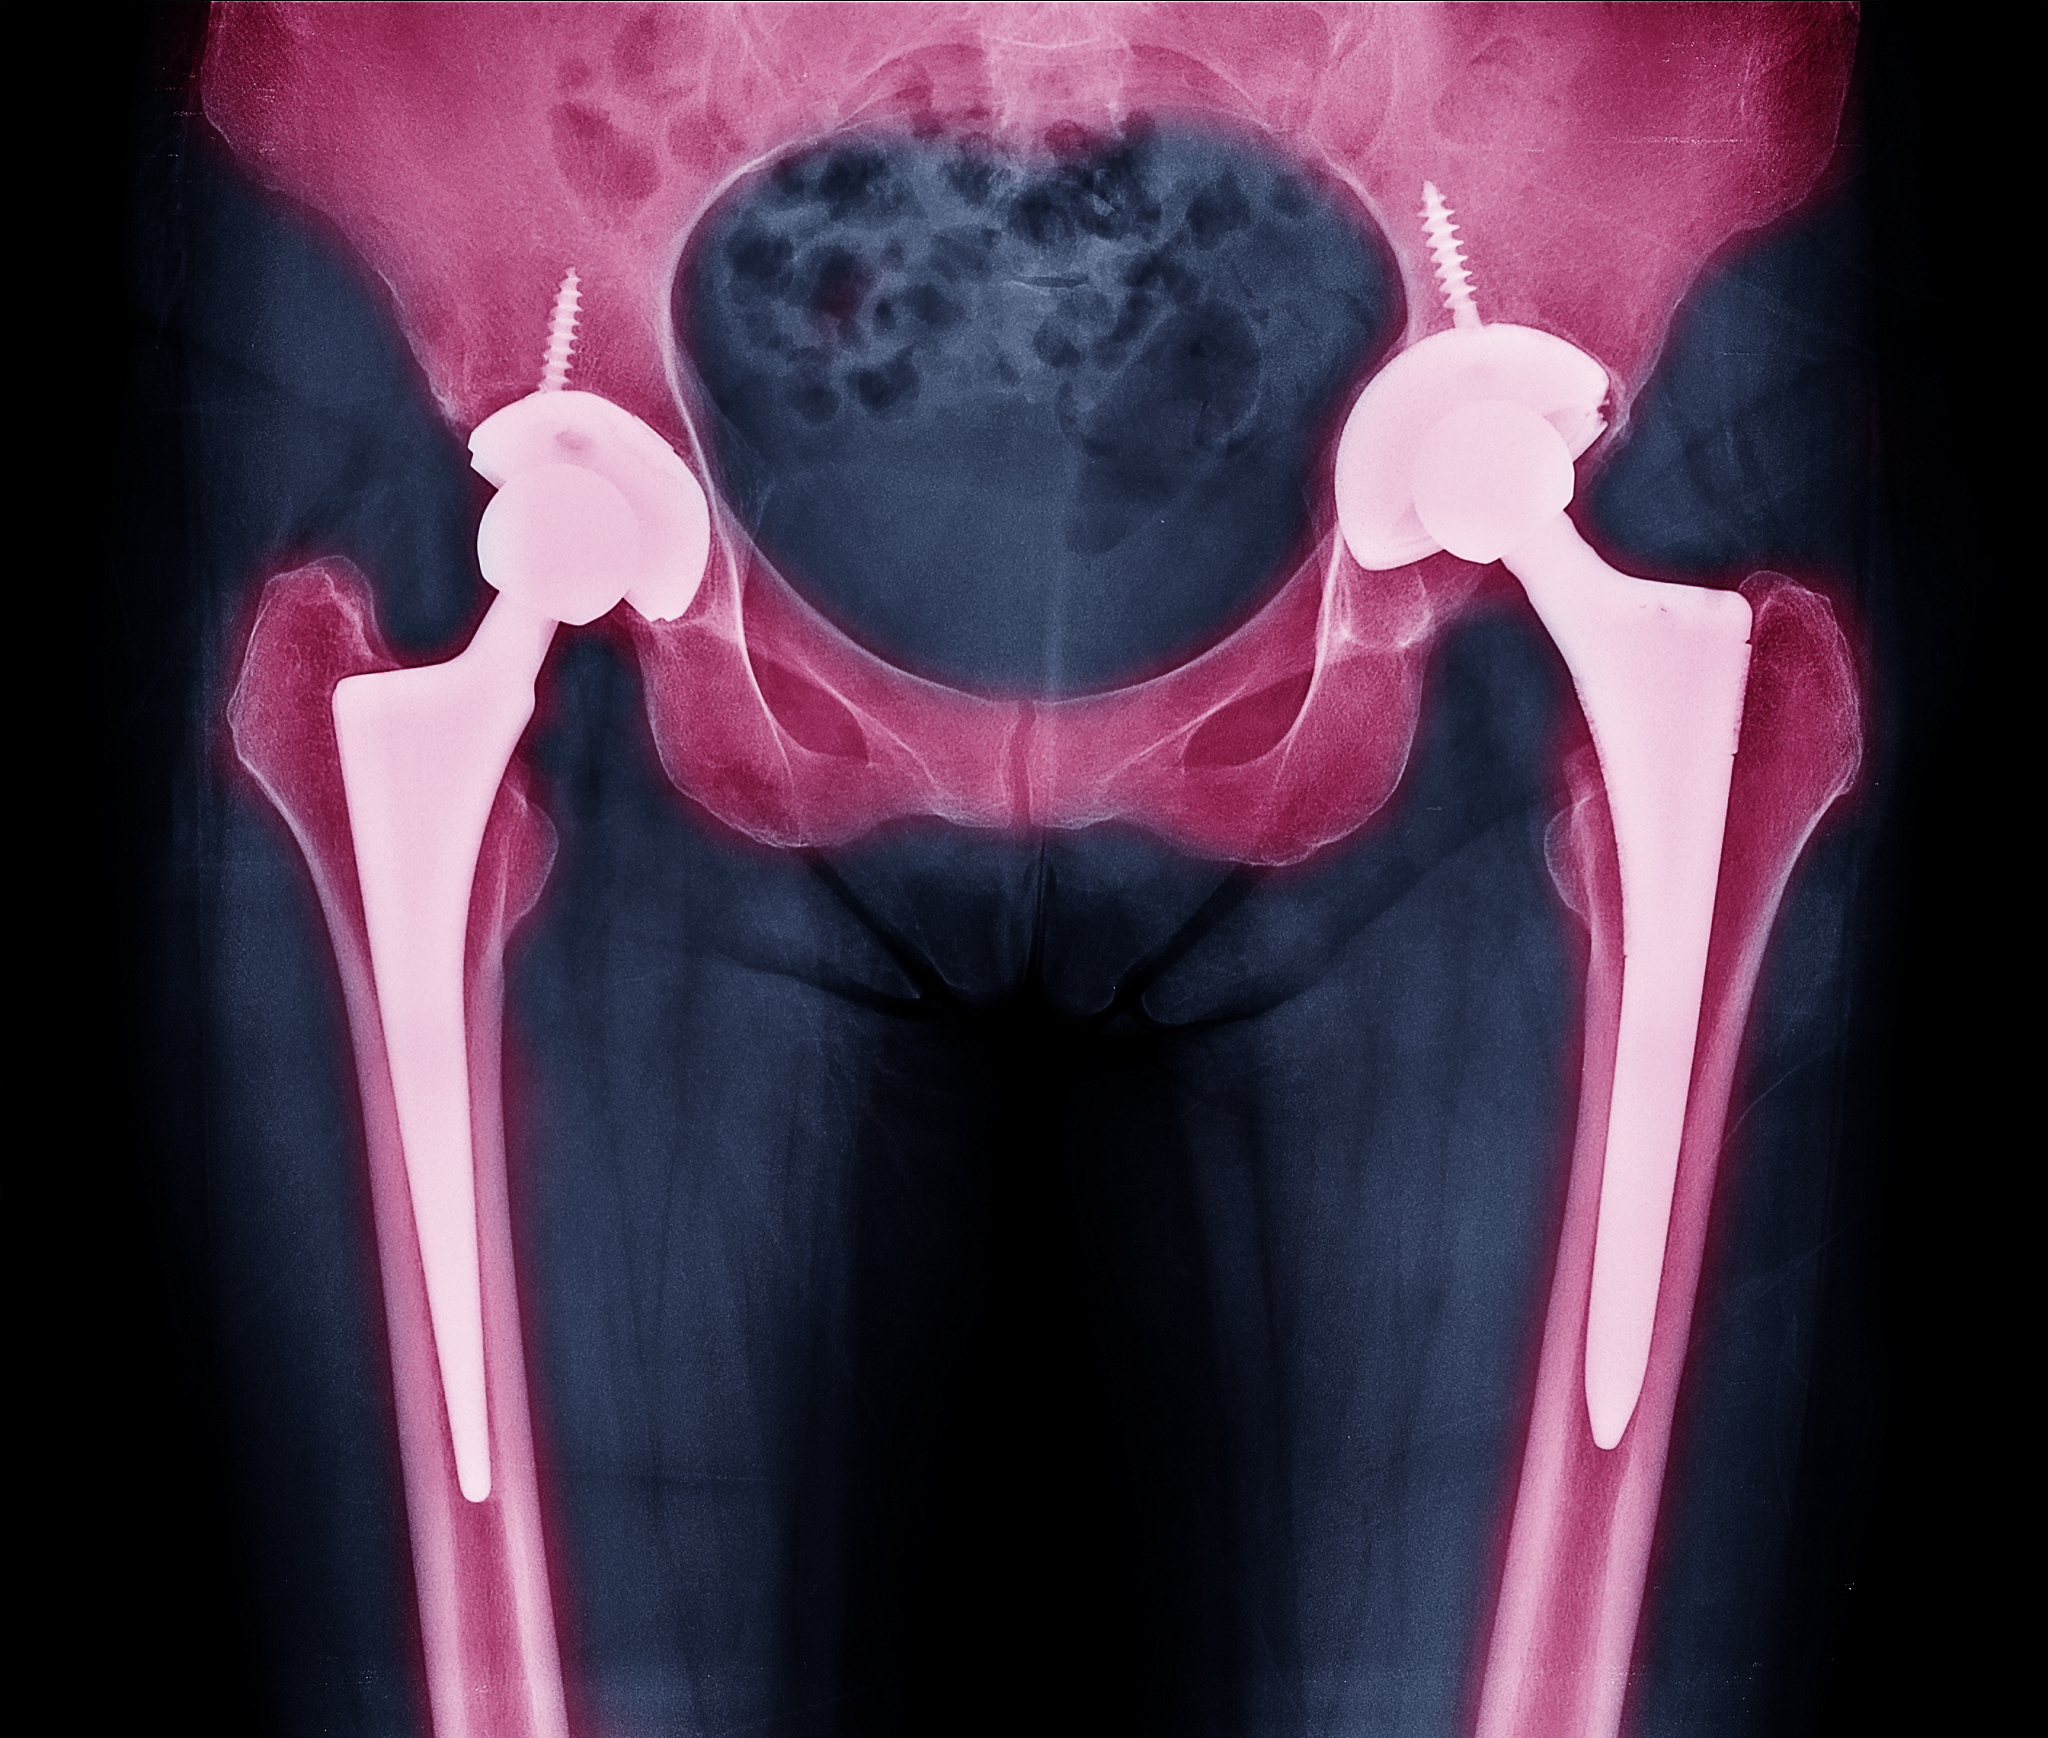

如何治疗骨质疏松伴病理性骨折?

治疗骨质疏松伴病理性骨折,需要综合考虑患者的年龄、身体状况、骨折部位和严重程度等因素。主要的治疗方法包括:

• 药物治疗: * 补钙和补充维生素D * 使用抗骨吸收药物,例如双膦酸盐类药物* 手术治疗: * 针对严重的骨折或畸形 * 常用的手术方式包括骨折复位、内固定和植骨等* 康复治疗: * 物理疗法,例如电刺激、热疗等 * 运动疗法,例如关节活动度训练、肌肉力量训练等 * 骨质疏松预防教育,帮助患者改变生活方式,预防再次骨折